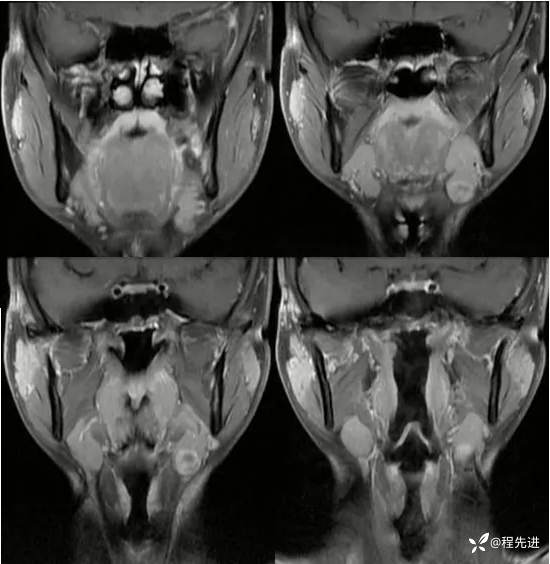

【患者信息】:男,21岁

【现病史及既往史】:发现左颌肿物2周

体格检查:左颌下触及肿物,约1.5*1.5cm,质硬,活动好

增强:

img

淋巴结肿大 (79)